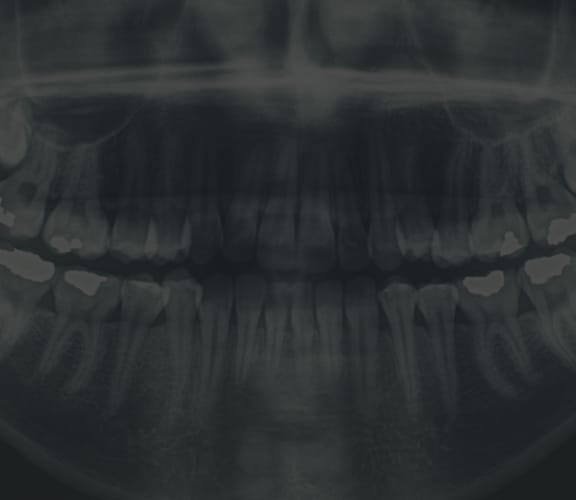

Tooth Extraction

When the extraction of a tooth is required:

During this time, it is important to think about a tooth replacement option. An extracted tooth leaves an open area in the jaw which, in time, allows the neighboring teeth to drift into the area where the tooth was extracted. This in turn, causes a chain reaction to all the surrounding teeth. Also, if you are considering placing an implant in the future, you should consider asking your dentist to place a bone graft at the time of surgery to preserve the bone width and height.